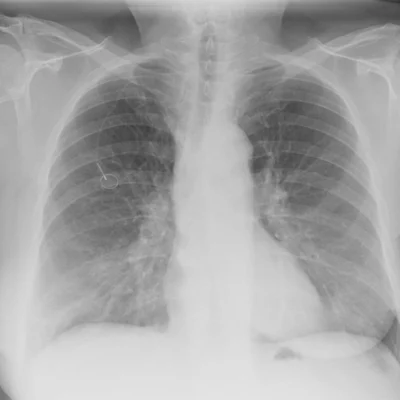

Most radiology divisions experienced decreased imaging volumes except for the divisions of thoracic and interventional radiology (IR). Thoracic radiology experienced sustained volumes as chest imaging, most notably portable radiographs, continued and even increased above baseline at times for patients with known or suspected COVID-19 pneumonia. IR also had sustained case volumes as surgical specialties deferred cases.

During NYC's initial surge in March and April 2020 a need for increased portable CXR capacity was seen across the health system. This challenge was met by immediately securing loaner units at no cost from multiple vendors. Prior to the surge, the hospital consisted of about 1,500 inpatient beds was performing on average 250 portable CXR's daily, whereas in March and April of 2020 the daily average was 380, an approximate 50% increase.